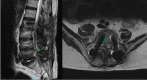

Spondylodiscitis is an uncommon but serious complication after spine surgeries, and its main etiologic agent is Staphylococcus aureus . Fungal infections are rare and mostly caused by Candida albicans . We report the clinical case of a 69-year-old male patient who underwent a L2-S1 arthrodesis for degenerative scoliosis correction. He presented an infection 2.5 months after the procedure, a spondylodiscitis at L5-S1 levels, caused by Candida parapsilosis . The treatment consisted of surgical material removal, tricortical iliac graft placement in an anterior approach (L5-S1), lumbopelvic fixation (from T10 to the pelvis) in a posterior approach, and drug treatment with anidulafungin and fluconazole. This last medication was administered for 12 months, with good clinical outcomes.